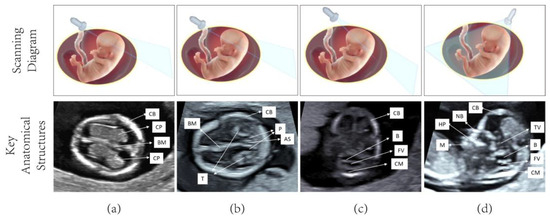

4.3.2. Model Visualization Results